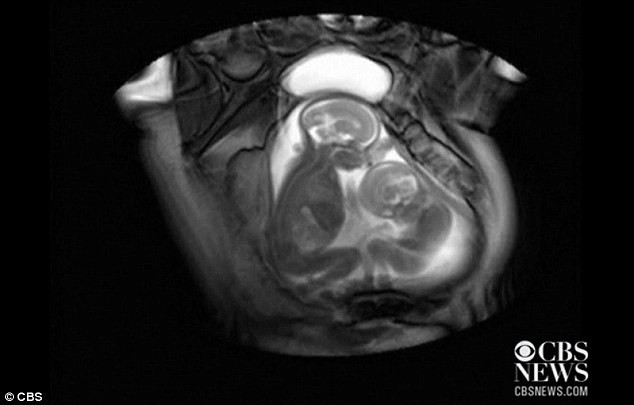

| Em bé lớn hơn phản ứng lại bằng cách cử động cơ hàm. |

Hội chứng này khiến khi sinh ra, các bé chênh lệnh nhau khá nhiều về trọng lượng. Những em bé nhỏ hơn thường bị thiếu máu, mất nước và xanh xao hơn. Trong khi đó, em bé sinh đôi lớn hơn lại nhận nhiều máu quá sinh ra huyết áp cao có thể dẫn tới suy tim.

Tuy nhiên, trong quá trình chẩn đoán căn bệnh cho cặp song sinh trong đoạn video, các bác sĩ đã phát hiện ra cảnh xung đột khá thú vị giữa hai em bé.